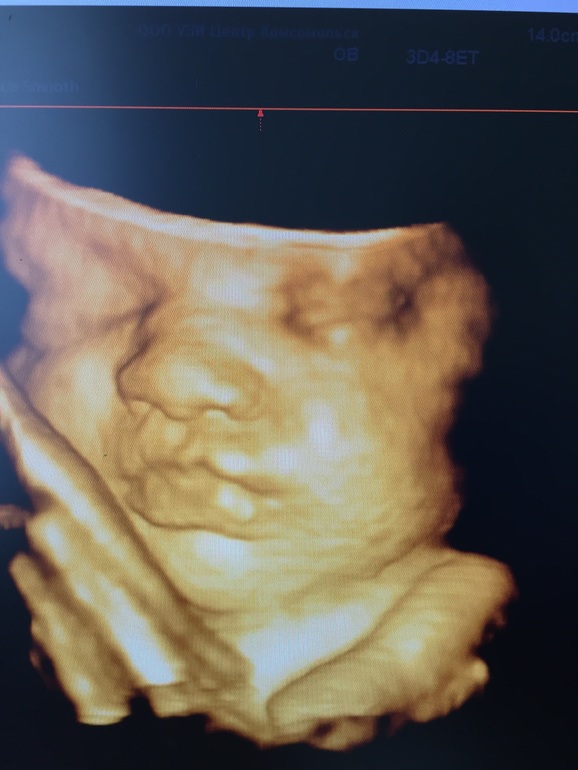

Привет девчонки! Я наконец сходила на 3d узи! Доктор попался хороший! Про него много лестных отзывов! Показал мне мою детюльку записал диск с фотками и видосами! Успокоил на счёт расширенного мвп! Теперь то я спокойна! Смотрю на детеныша и невольно улыбаюсь)